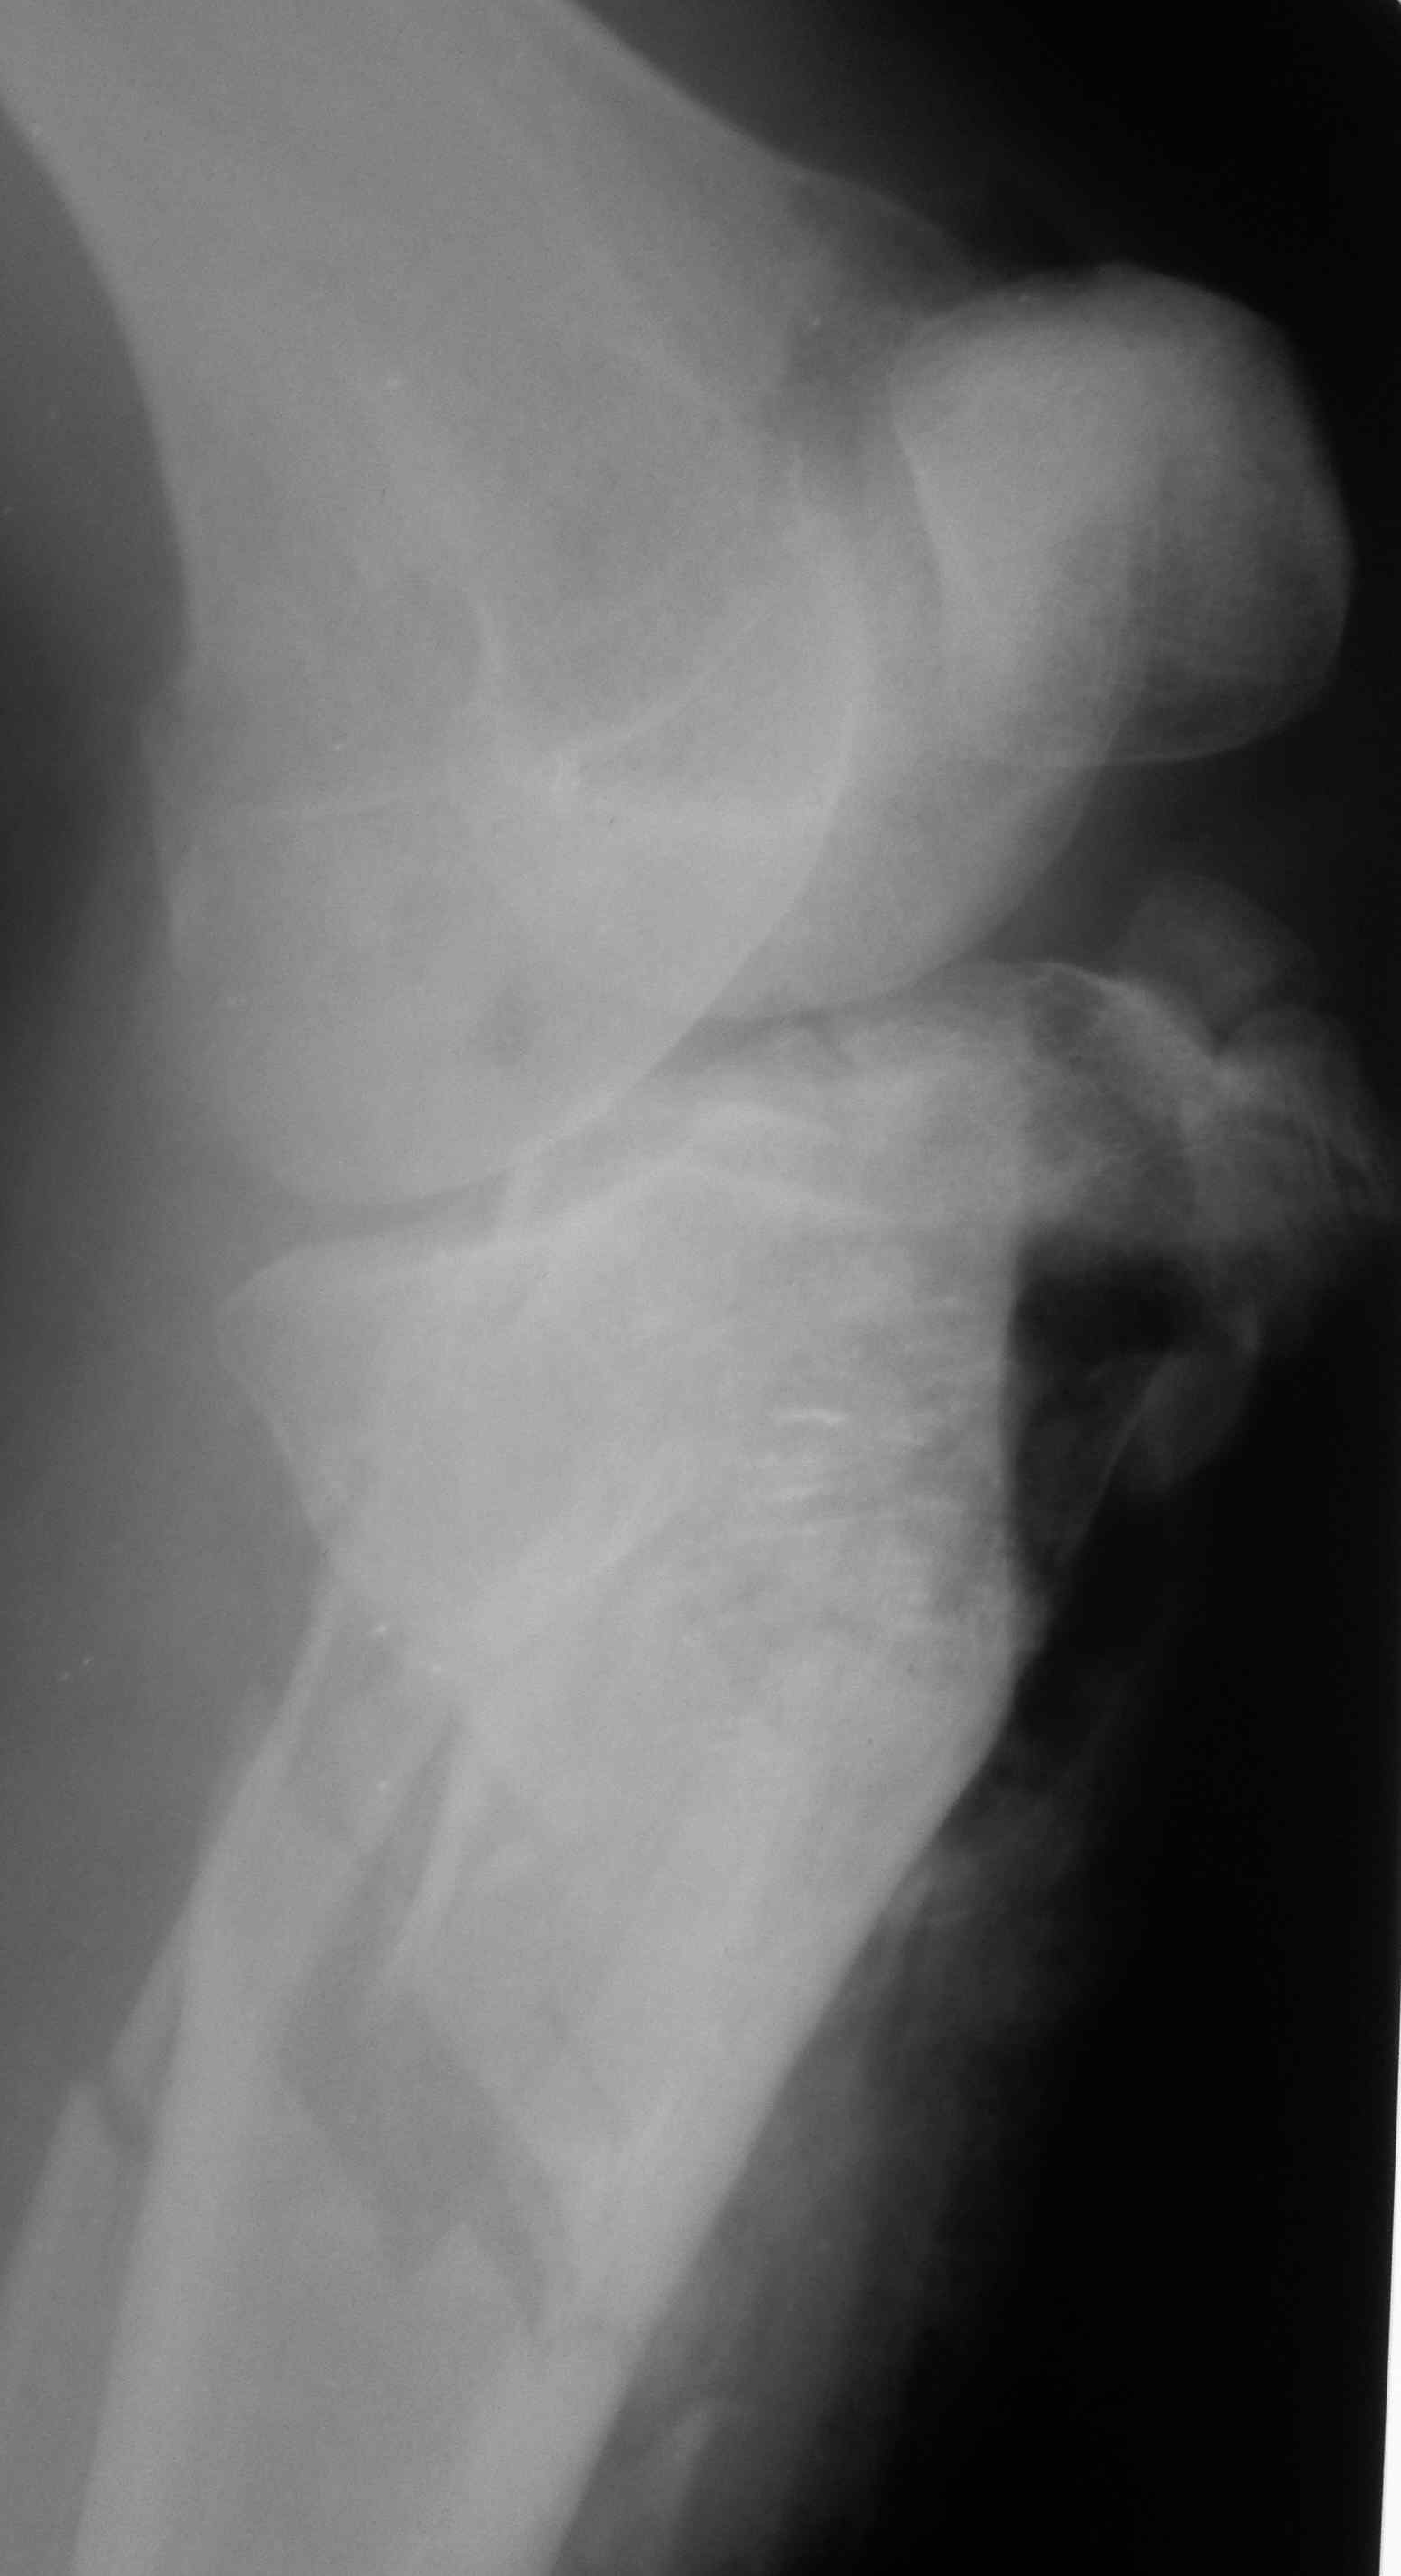

[Ortho] перелом проксимальной тибии + вывих бедра

Высокоэнергетическая травма около недели назад, мужчина 39 лет

По месту поступления вывих бедра вправлен, ПХО раны открытого перелома

б/б кости, скелетное вытяжение. В настоящее время рана заживает неплохо,

небольшое количество серозно-геморрагического отделяемого, состояние

мягких тканей неплохое. Планируем остеосинтез плато из 2-х доступов по

заживлению раны.

1 смущает фрагмент плато в проекции раны, насколько удобно его будет

ловить, попробовать полечить в аппарате + винты

закрыто?

2 часть задней стенки в суставе, такое впечатление, что она больше ямки

и подвывихивает сустав или это ошибочное впечатление?

3. насколько целесообразно искать этот фрагмент во впадине и пытаться

засинтезировать задний край при наличии довольно выраженного FAI?